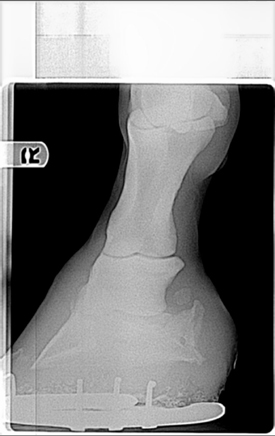

Posted on Tuesday, Mar 22, 2005 - 11:21 pm: Aileen the pictures are too small for me to make any detail out on. Could they me made larger? Start with the originals and just reduce them to a width of 500 pixels, maintaining the aspect. Then reduce the image to just below 64K. We are traveling right now but I will look at them this weekend.DrO |

Posted on Wednesday, Mar 23, 2005 - 10:39 am: I'm having difficulty, but try this one. I could also email them to you, that way you'll get the full xray. Let me know if that's ok. |

Posted on Friday, Mar 25, 2005 - 10:20 am: I can see he has remarkable calcification of the lateral cartilages (probably not significant) and the 10:41 image appears to have something going on around the coffin joint, but I cannot make out any detail.These images were originally 8 by 10 and for the detail we need, for the type judement you want, it is going to require a full size original on a screen, only then can I compare these lesions with those I have seen in the past. Let's try to get this on firmer ground. What lesions did your veterinarian diagnose from the above radiographs that made him make the above statement? DrO |

Posted on Tuesday, Mar 29, 2005 - 11:22 am: You appear to be making sense but I don't understand the vets thought about degenerative joint disease of the coffin bone bone healing: this is chronic arthritis. Are you sure you are on the same wavelength with your vet?Looking at your radiographs only raises more questions. Looking at rf2, which is an oblique of the foot, at first glance looks like changes consistant with coffin jt arthritis but...we have to remember that the lateral cartilages are ossified. For those follwing this discussion it is the 10:41 am radiograph above. I cannot be sure we are not seeing the overlying lateral cartilage, making it appear that the joint has developed remarkable osterphytes. In fact I find this a likely explanation but would require further radiography to prove or disprove. I don't see evidence of DJD of the coffin joint evident on the lateral (straight from the side) or ap (the one taken directly from in front of the foot) and the other obliques are too underexposed to read this aspect of the study. Though we do not see it in the other views, often the first place to see these changes are in the oblique shots. I recommend the vet take a series of obliques that slowly work around the foot to differentiate these 2 possiblilities. Yes you can palpate the side bone. Look on the ap radiograph and it will show you exactly where to feel them. DrO |